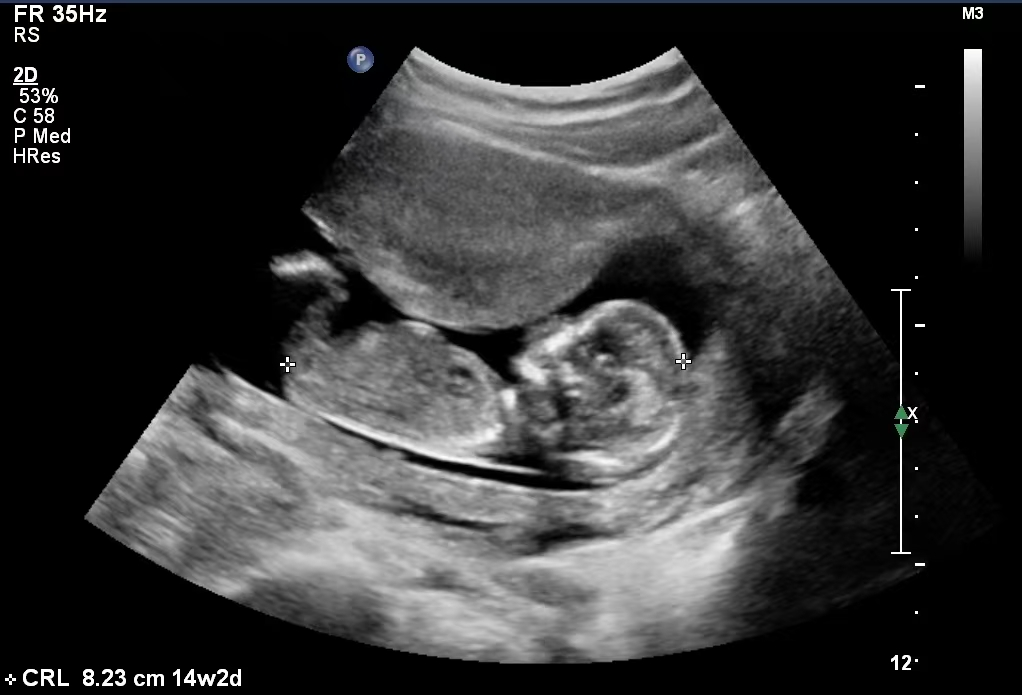

“MALBAC-Baby”在胎儿期B超图

2014年9月19日,世界首例经MALBAC基因组扩增高通量测序进行单基因遗传病筛查的试管婴儿顺利诞生。